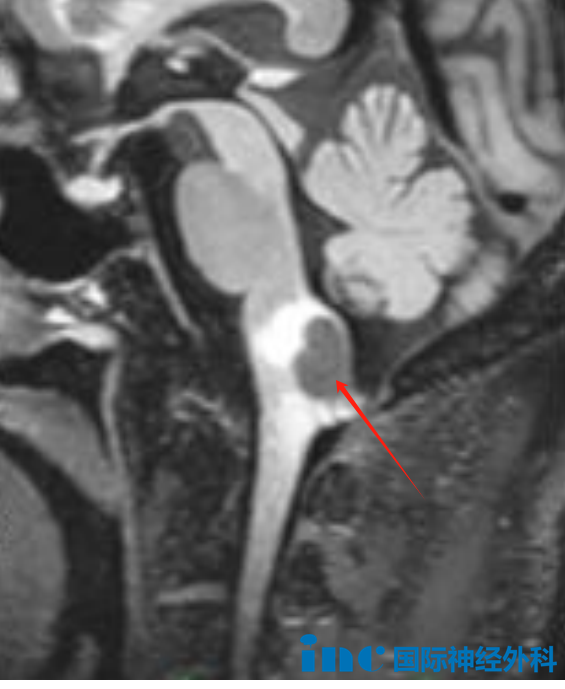

當(dāng)陳先生發(fā)現(xiàn)小指麻木時(shí),他以為只是頸椎問題。誰曾想,這場“麻木風(fēng)暴”在兩個(gè)月內(nèi)向全身蔓延。進(jìn)一步檢查的結(jié)果如同驚雷:延髓背側(cè)占位性病變正在蠶食他的“生命中樞”。病變位于延髓這一關(guān)鍵生命區(qū)域,并造成占位效應(yīng),腦干內(nèi)存在彌漫性水腫,因此明確需要進(jìn)行手術(shù)治療。

延髓背側(cè)占位性病變

然而,在延髓區(qū)域,絕大多數(shù)患者面臨著這樣的困境:“沒有醫(yī)生愿意為我手術(shù)!延髓腫瘤切除手術(shù)是在‘賭命’,就算成功切除大概率要長期臥床靠呼吸機(jī)生存,甚至,很可能會(huì)在手術(shù)臺上永遠(yuǎn)醒不過來……”面對這一度被稱為“手術(shù)禁區(qū)”的區(qū)域,巴教授卻給出了截然不同的答案:“唯一可取的治療方案是手術(shù)切除,而且這類手術(shù)對我而言難度不大。”

30年深耕腦干手術(shù)的經(jīng)驗(yàn),讓這位國際神外大咖能夠游刃有余地在“生命禁區(qū)”精準(zhǔn)操作。在他手中,延髓腫瘤手術(shù)不再是“賭命”,而是一場精心策劃的“生命保衛(wèi)戰(zhàn)”。從術(shù)前手術(shù)入路設(shè)計(jì),到顯微鏡下毫厘不差的精細(xì)操作;從神經(jīng)功能的保全,到術(shù)后重歸正常生活——他不斷突破著一個(gè)又一個(gè)曾被視為禁區(qū)的醫(yī)學(xué)極限。